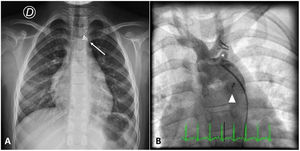

At admission her chest X-ray was normal except for the presence of two surgical clips apical to the cardiac shadow (Figure 1A). Aortic angiography revealed a PDA and, unexpectedly, two vascular clips occluding the left subclavian artery (Figure 1B). Retrograde PDA closure was successfully performed with implantation of an Amplatzer Duct Occluder II. Unfortunately, the clip ligation was considered irreversible. An echocardiogram confirmed ductus closure with no residual leaks. She was discharged home clinically well.

In our case, X-ray analysis raised suspicions of incorrect ligation due to abnormal apical clip position above the aortic knob. Post-procedure angiography (Figure 1B) clearly confirmed the difference between the closed PDA and the abnormal clip position.